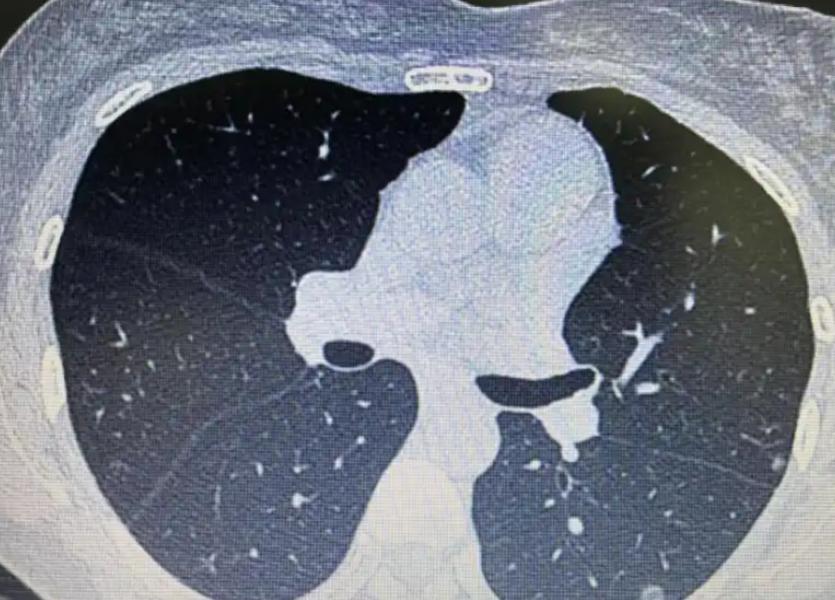

張おじさんのようなCOPD 患者の多くは、日々「いつもの習慣」に従って生活していますが、その中には実は静かに病状を悪化させている習慣も含まれていることに気づいていません。

では、COPD 患者は毎日どのように過ごせば安全なのでしょうか?朝に食べてはいけないものは何でしょうか?昼と夜にはどのような“見えない危険地帯”が頻繁に踏み込まれているのでしょうか?その根本的な原因をたどると、答えは多くの人の予想外のものであることがわかります。